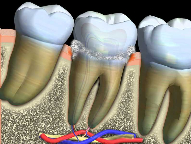

Recurrent decay (decay around existing fillings) can be detected during recall exams. If left untreated, the decay will spread underneath the filling and the tooth may require extensive treatment.